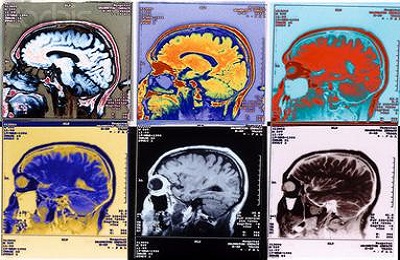

Принцип работы компьютерного томографа основан на использовании рентгеновского излучения небольшой мощности. При проведении КТ-ангиографии аппарат позволяет сделать серию снимков кровеносной системы органа послойно. На основании большого количества срезов, сделанных в разных плоскостях, компьютер строит трехмерную модель кровеносной системы органа, например, головного мозга или нижних конечностей.

- обнаружить новообразование в головном мозге и дифференцировать его (злокачественные опухоли захватывают контрастное вещество более активно в сравнении с доброкачественными);

- визуализировать участок головного мозга, который подвергся ишемии (используется для выявления инсультов головного мозга).